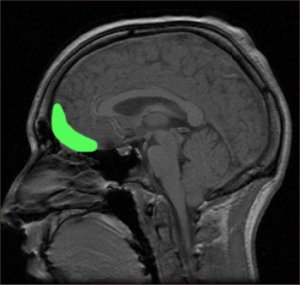

Analizirane su tri karakteristike mozga, uključujući volumen područja koje se naziva orbitofrontalni korteks (OFC), povezanost tog područja s ostalim područjima mozga te strukturalni integritet moždanog tkiva. OFC se inače povezuje s osjećajima ovisnosti, sposobnosti donošenja odluka te povećanjem moždanih veza. Provedeni kognitivni testovi su pokazali da kronični korisnici imaju niži kvocijent inteligencije (IQ) dok je skeniranje mozga pokazalo smanjenje volumena mozga u području OFC-a, no istraživači kažu da ova dva rezultata nisu međusobno povezana. Također je otkriveno da je ovo smanjivanje mozga značajnije u skladu s dobi početka korištenja marihuane, odnosno, što je osoba bila mlađa kad je konzumacija započela, skupljanje mozga je bilo veće.

No, tim je također pronašao dokaz da mozak kod kroničnih korisnika kompenzira to skupljanje tkiva aktivnim povećanjem povezanosti različitih područja mozga i porastom strukturalne cjelovitosti tkiva. To se povećanje događa čim osoba počne koristiti marihuanu i postaje značajnije u skladu s češćim korištenjem. Sve do određene točke. Nakon šest do osam godina kronične upotrebe marihuane, ova povećana mogućnost povezivanja počinje opadati i ostavljati smanjeni OFC te slabu povezanost mozga koja je jedva iznad prosjeka.